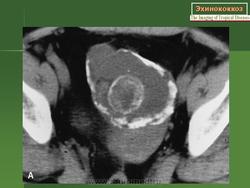

Эхинококкоз

Splenic hydatid cyst </p> <p>

ID: 10637 Hydatid cyst of the spleen Dr Ruslan Esedov - 28 Aug 2010 CT demonstrates a very large cystic mass in the spleen with peripheral c...